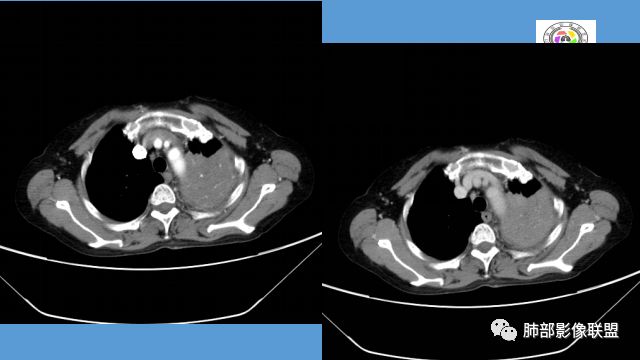

中年女性,反复咳嗽咳痰4月,加重半月,咳嗽,咳黄痰。胸CT:左肺体积缩小,左肺上叶病变,病灶内可见支气管征,病灶边缘可见棘突样改变,病灶周围可见结节状卫星灶,纵隔可见淋巴结肿大,部分淋巴结可见钙化灶。增强CT病灶内可见低密度坏死区,冠状位病灶内支气管可见扩张,病灶整体呈收缩,考虑患者为良性慢性感染性病变,结核?放线?,建议支气管镜检查。

中年女性,反复咳嗽咳痰4月。胸CT:左肺上叶块状病变,病灶内可见支气管征,边缘见棘突样改变,周围可见结节状卫星灶,纵隔可见淋巴结肿大,部分淋巴结可见钙化灶。增强CT病灶内可见低密度坏死区。病灶整体呈收缩,考虑为良性病变,结核可能性大,建议支气管镜检查。

晨读:左肺上叶实变,边缘不整,部分膨隆,其内支气管有狭窄有扩张,周围小叶间隔增厚,左肺下叶背段可见气腔结节,树芽征,边缘模糊,肺门及纵膈淋巴结钙化,考虑结核。鉴别肺炎型肺癌。